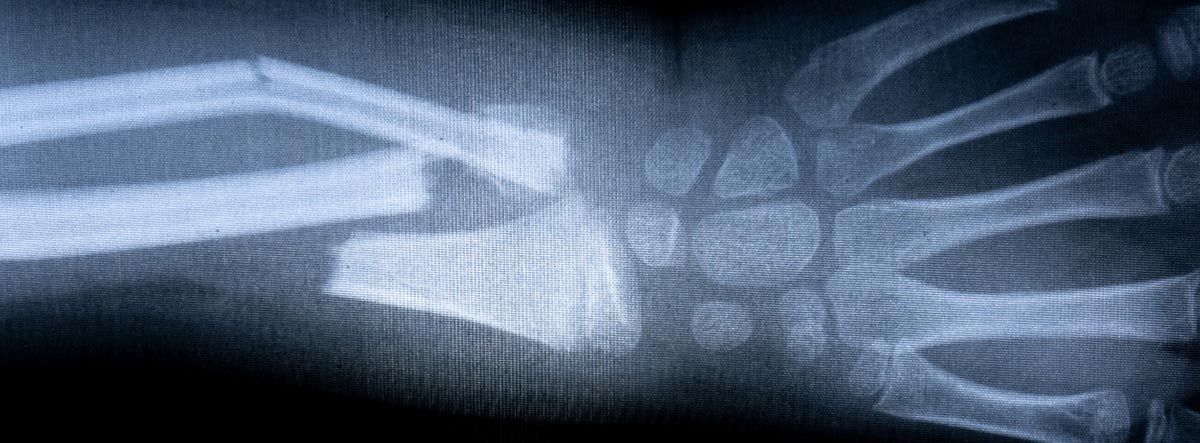

La prueba diagnóstica por excelencia en ambas será la radiografía. En algunos casos muy concretos puede precisarse el TAC o la RNM para acabar de estudiar mejor la lesión.

Para distinguirlas con propiedad, diremos que una fisura ósea es una fractura de hueso incompleta. Se caracteriza por no existir una separación de los bordes, ni haber ningún fragmento óseo. Podríamos decir que es como una herida o grieta que se produce en el hueso.

Por su parte, la fractura se produce cuando el hueso se ha roto por completo produciendo discontinuidad entre los dos extremos de éste.